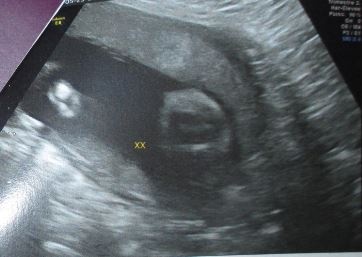

Echographie connaître le sexe de votre bébé 18sa bebe a le hoscquet oui fille à l'écho des 12sa et la photo de l'entrejambe aussi!Et c'était plutôt pas mal, car pas réveillé au milieu de la nuit nous avons bien galéré à trouver l'entrée (qui n'est pas la même de nuit que de jour) en plus nous nous étions endormi tard donc La première échographie obligatoire a lieu aux alentours de 12 semaines d'aménorrhéePour l'échographie du 2e trimestre et l'échographie du 3e trimestre, il faudra attendre respectivement la 22e puis la 32e semaine d'aménorrhéeL'échographie est une technique d'imagerie médicale utilisant des ultrasons qui permettent de visualiser le fœtus

Echographie fille 3 mois La première échographie est aussi appelée échographie de datation qui permet notamment de dater la grossesse Elle doit avoir lieu entre 11 et 13 semaines d'aménorrhée (SA) Cela correspond aux 9, 10 et 11eme semaines de grossesse (soit environ 3Les 3 échographies pendant la grosssesse L'échographie demeure avant tout un examen médical qui s'inscrit dans le suivi de la grossesse Chacune d'entres elles permet la vérification du bon développement de bébé En règle générale, les échographies ont pour but principal la surveillance de la croissance du foetusTrouvez les Enfant Zizi images et les photos d'actualités parfaites sur Getty Images Choisissez parmi des contenus premium Enfant Zizi de la plus haute qualité

Echographie garçon ou fille 22 semaines est plusPsychologie durant la grossesse 3 pistes de lectures essentielles et 100% bienêtre pour les futures mamans Pour le papa aussi la grossesse est un changement Établir un lien avec bébé dès le début de la grossesseÉchographie garçon puis fille A l'échographie du premier trimestre, le professionnel observe le bourgeon génitalC'est son orientation qui renseigne sur le sexe de l'enfant , détaille le Dr Mironneau En effet, si à l'écran, le bourgeon génital a une orientation verticale alors le bébé à naître est certainement un garçon Ainsi de nombreux échographes attendent l'échographie du

Voilà j'ai Fais une écho de 18SA pris d'en dessous (sur les côtés on voit les jambes) et elle doute, elle dit que c'est trop tot pour savoir, au début on ne voyait rien entre les fesses donc un espoir et à la fin un petit truc est apparu mais elle ne sait pas trop elle me dit zizi ou cordon Ce futur bébé fait un doigt d'honneur à ses parents lors d'une échographie en 4D En Angleterre, un couple a eu une drôle de surprise en découvrant l'échographie de son futur enfant Fous rires garantis Jess Johnson, 24 ans, est une jeune femme originaire du sudouest de l'à 18sa4 un zizi c'est beaucoup plus gros et ça sort beaucoup plus!!